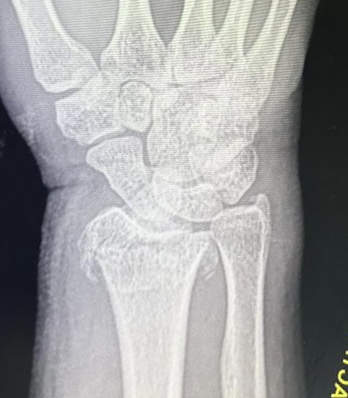

Клинический случай: внутрисуставной перелом дистального метаэпифиза лучевой кости — до операции